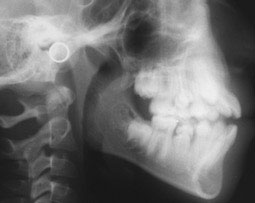

Analyse céphalométrique

avant traitement Mars 2000 SNA 87°

SNB 85° ANB 2° GoGn/SN 30° Occl/SN 13° I/NA 33°/7mm i/NB 38°/8mm FMA 29° IMPA 102° i/Apog 7 mm AoBo -3 mm |

Enfin, son profil était convexe avec une projection des tissus mous vers l’avant (Fig. 7, 8).